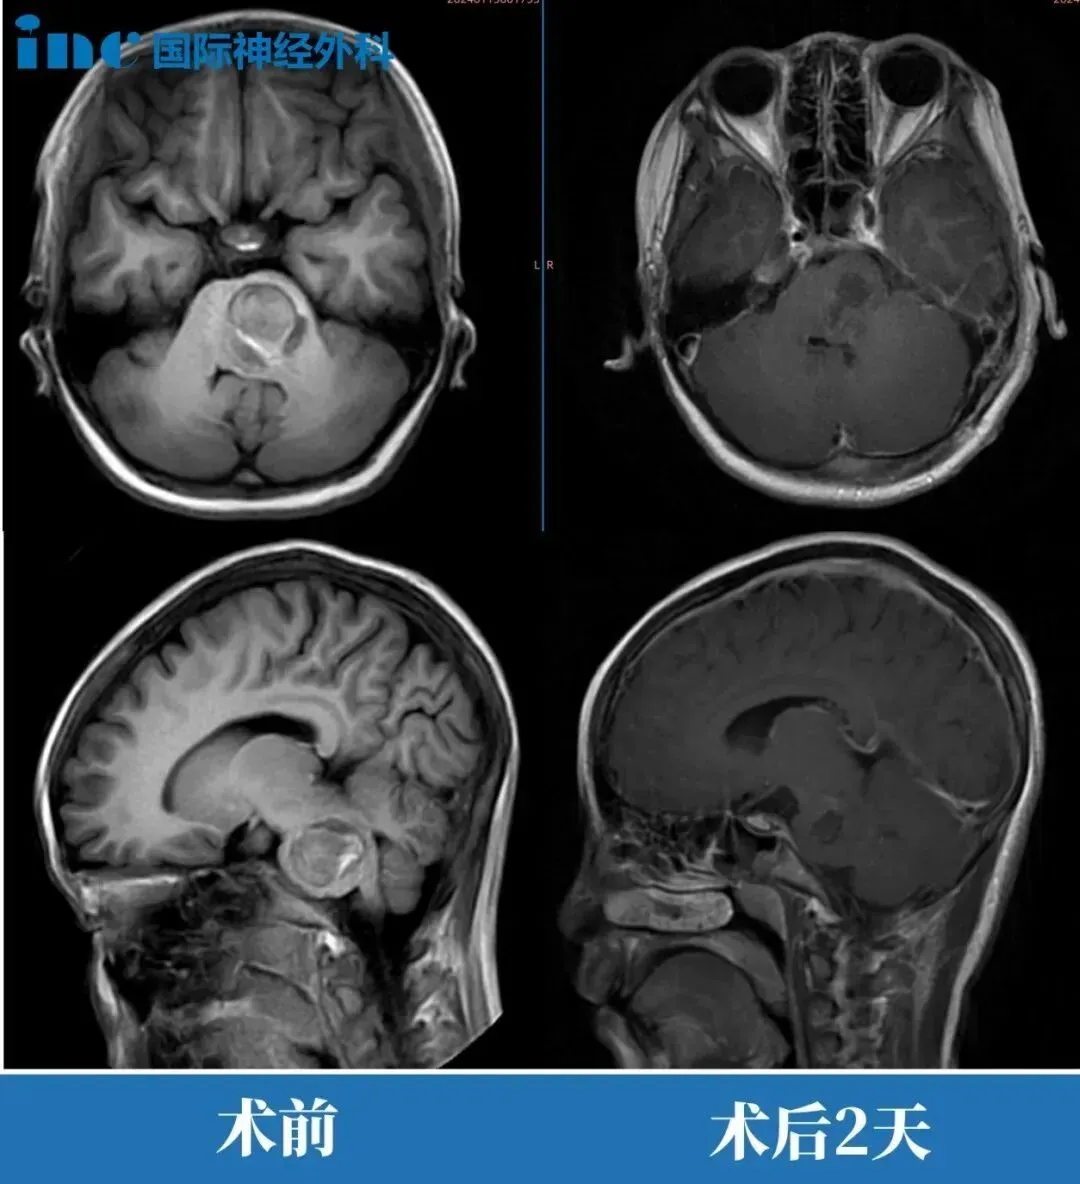

术前与术后2天的影像对比

“影像学片子显示结果非常好,脑干形态已经恢复正常,一年后回来复查即可。”巴教授的话语,彻底打消了夫妻二人心中最后的顾虑。